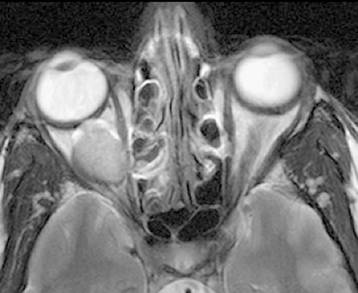

Figure 14.3.3: Axial T2-weighted image.

The vitreous is hyperintense (bright) relative to the orbital fat. The lesion seen in the prior two figures is also bright but in some cases may be isointense with the surrounding fat.